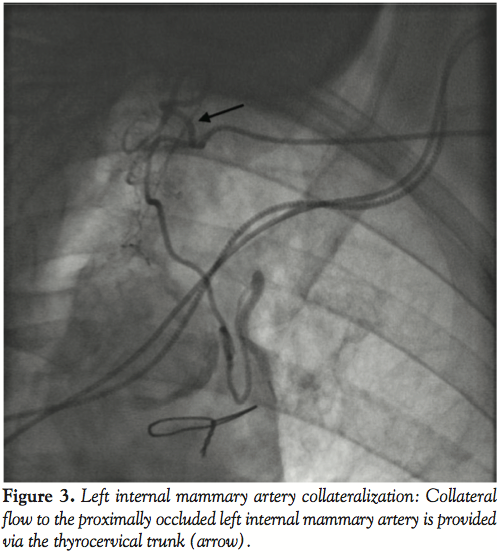

Collateralization of an Occluded Left Internal Mammary Artery Coronary …